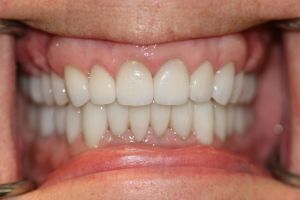

Before

After